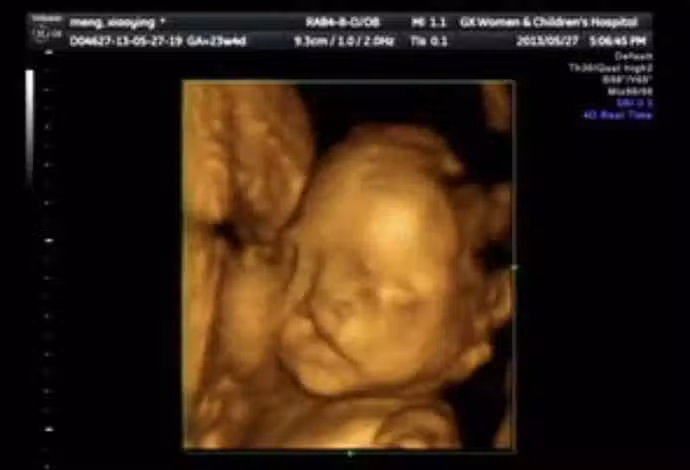

懷孕6個月!23歲孕媽照超音波「寶寶一直在笑」 醫生皺眉勸:「孩子不能留」‼️

圖片來源:ETtoday

突如其來的消息,讓年輕媽媽瞬間崩潰,不明白自己在孕期明明很注意了,為何還會有問題呢?後來經過詳細了解後,醫生終於找到了問題根本,原來女子在婚前的生活十分豐富,不但經常和朋友喝酒玩樂,甚至還菸不離手。雖然說婚後減少了許多夜生活,但是吸菸這麼多久,早就已經難戒掉了,「我在懷孕後也有繼續抽,身邊也有孕期抽菸的朋友,她們生下來的孩子都很健康」,所以她一直以為沒事,抱著僥倖的心態,結果竟然發生了不可挽回的憾事。